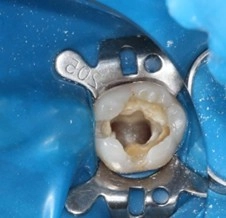

患者因劇烈牙痛就診。經檢查,確認為嚴重蛀牙已經穿透牙釉質與牙本質,感染深達牙髓腔神經,引發不可逆恢復的牙髓炎。

- 治療步驟: 必須立即進行根管治療(俗稱抽神經),清除發炎或和壞死的牙髓組織,徹底清創並緊密封填根管系統,以保留這顆珍貴的自然牙。

- 無菌保障: 我們在治療過程中全程使用橡皮布障隔離患齒和口腔環境的細菌,創造無菌的治療環境,大幅提高治療的成功率和預後。